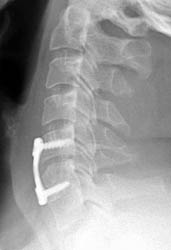

Lateral radiograph taken 3 months post-operatively for a routine

survey. Careful examination of the positioning of the screws relative to each

other one can note that on the prior film, the screws are parallel to each

other. Now, the screws converge anteriorly slightly, consistent with graft

collapse.